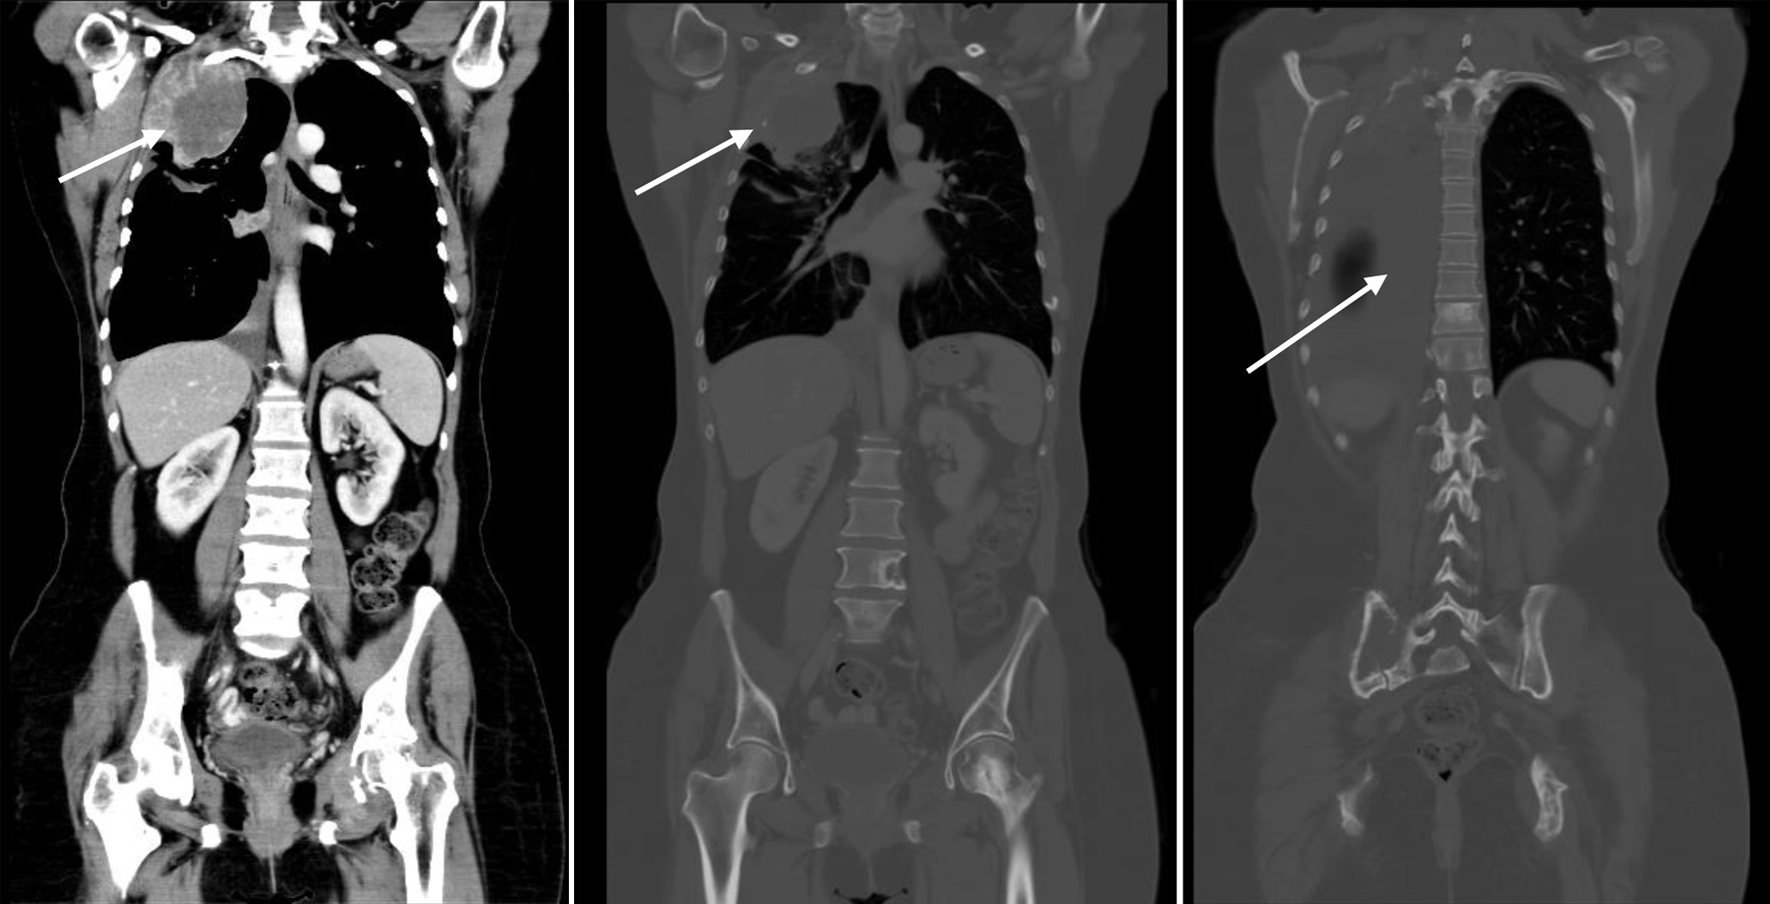

Imaging in February 2023 showed marked disease progression, manifested with enlarging extraosseous soft tissue component associated with destructive bony lesion involving the right second rib and left acetabulum, enlarging multifocal bilateral metastatic pulmonary lesions, and right-sided pleural effusion with pleural nodular thickening, suspicious for pleural carcinomatosis (Fig. 4).

![]() Click for large image | Figure 4. CT scan showing disease progression (February 9, 2023): enlarging extraosseous soft tissue component associated with destructive bony lesion involving the right second rib and left acetabulum, enlarging bilateral pulmonary lesions, and moderate right-sided pleural effusion with new right pleural nodular thickening, suspicious for pleural carcinomatosis (arrows). Beta-hCG level was elevated (8.43 mIU/mL). Beta-hCG: beta human chorionic gonadotropin; CT: computed tomography. |

β-hCG level was incidentally found to be mildly elevated on February 7, 2023 (8.43 mIU/mL). Repeating the test on March 12, 2023, the level remained elevated (8.44 mIU/mL). Brain MRI was done with no evidence of intracranial space occupying lesion or abnormal contrast enhancement.